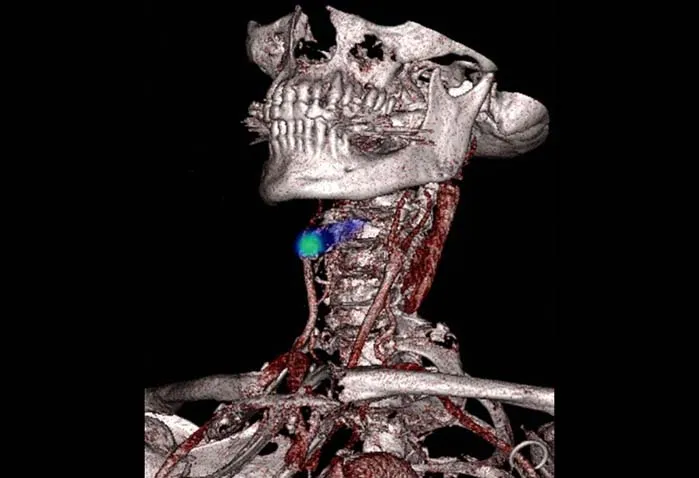

تشخیص حملهی مغزی

این تصویر به زیبایی یکی از مرگبارترین نقاط دو سانتیمتری در آسیبشناسی بدن انسان را نشان میدهد. همچنین ابزاری بسیار عالی برای تشخیص علت بروز حوادث مربوط به عروق مغزی یا حملههای مغزی به حساب میآید.

این تصویر پزشکی یک رگ خونی مسدود شده در گردن یک فرد را به رنگ سبز نشان میدهد. این رگ خون را به مغز منتقل میکند. اگر مسدود شود ممکن است قسمتهایی از مغز آسیب ببینند و خوب کار نکنند.